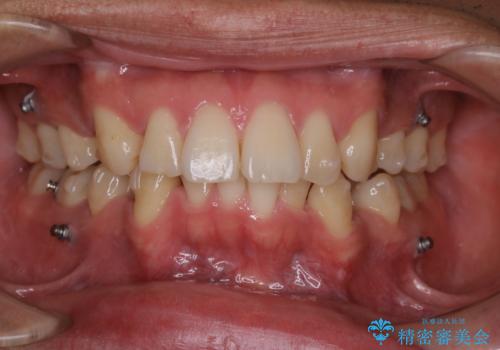

矯正中は汚れが付きやすいため、着色がとても多く付いていました。

抜歯したスペースや装置の周りの磨き方などとても難しため、定期的にクリーニングをおすすめします。